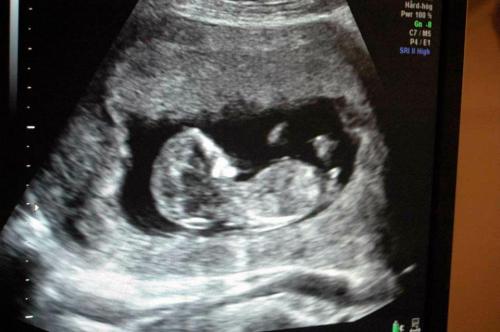

Eva Lotta sedang memeriksa bayi kami. Foto ini kami cetak dan kami jadikan hadiah untuk Eva Lotta, sebagai tanda terima kasih kami. Dia senang sekali menerimanya.

Istri saya sedang diperiksa oleh Eva Lotta.

Karena istri saya sudah berumur lebih dari 35 tahun, Eva Lotta menyarankan pemeriksaan yang lebih mendetail untuk ibu dan si janin. Kehamilan di usia ini memiliki peluang besar terkena penyakit ‘down sindrom’. Eva Lotta membuatkan jadwal pemeriksaan di puskemas lain yang memiliki perlengkapan lebih lengkap.

Di hari yang telah ditetapkan, istri saya diperiksa di puskesmas yang sudah ditunjuk tadi. Pemeriksaannya sangat lengkap, termasuk test darah dan pengukuran janin menggunakan USG. Pemeriksaan ini dilakukan oleh seorang bidan berpengalaman dan seorang dokter kandungan. Test ini memakan waktu cukup lama, dan hasilnya keluar seminggu kemudian. Alhamdulillah, janin kami sehat, dan kemungkinan terkena down sindrom sangat kecil.

Pemeriksaan janin dilakukan dengan teliti oleh bidan dan dokter kandungan.